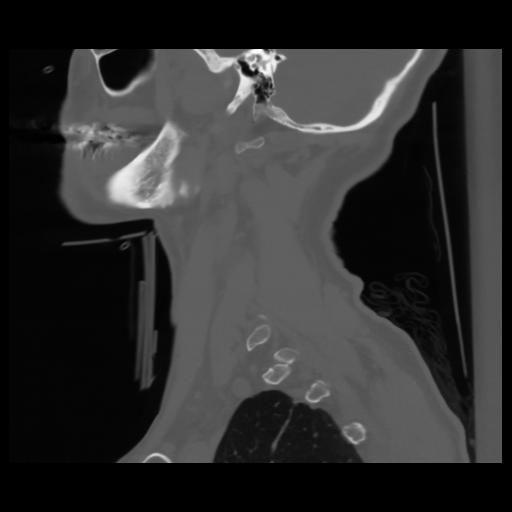

14 P.BLANDAS,,Sagittal,2.000,P.BLANDAS,Sagittal,